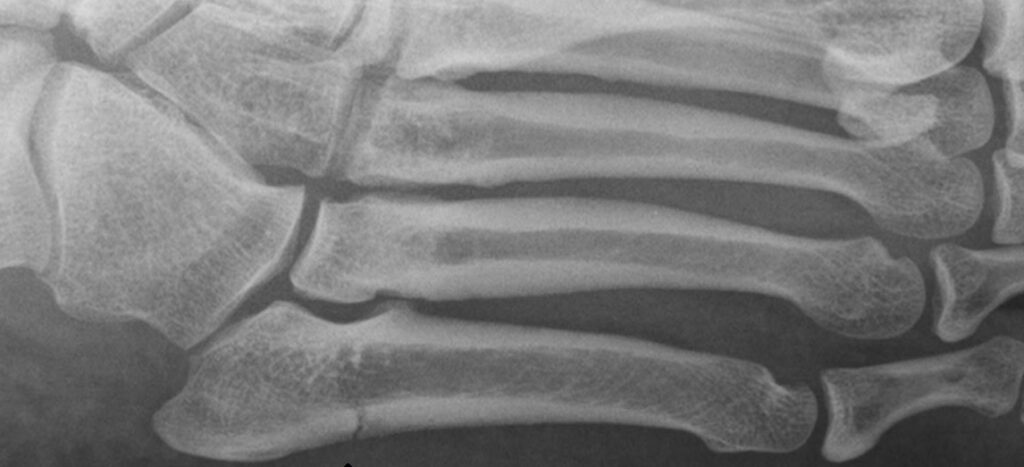

Vamman tai leikkauksen jälkeen kivulta ei voi kokonaan välttyä, eikä ole syytäkään. Jutallakin ollut vamma, niin sanottu Jonesin murtuma, on sijaintinsa takia (jalkaterän ulkosivu) usein haastava kuntoutettava. Tietyissä tilanteissa ja sopivissa määrissä kiputuntemukset muun muassa harjoittelun aikana ovat täysin hyväksyttyjä ja jopa suotavia. Kuntoutuksesta puhuttaessa kipu harjoittelun aikana ei ole automaattisesti huono asia, eikä kivun ilmaantuminen tarkoita sitä, että jokin olisi menossa rikki. Kipu on myös tärkeä mittari arvioitaessa liikkeiden vaikutusta ja kuntoutuksen etenemistä. Kivun arviointi auttaa fysioterapeuttia arvioimaan harjoitteiden vaikuttavuutta ja helpottaa kuntotasoon sopivien harjoitteiden valintaa sekä jatkosuunnitelman tekemistä. Kivun pysyessä sopivalla tasolla, ei se aiheuta lisävahinkoa, eikä sitä tarvitse pelätä. Tämä on ehkä tärkeimpiä asioita, joita fysioterapeutti voi sinulle opettaa.

Ns. Jonesin murtuman kuntoutuksessa on oman kokemukseni mukaan kahta erilaista kipua: jomottavaa ja vihlovaa kipua. Jomottava kipu on ok, ja se kertoo sopivasta rasituksesta. Jomottavan kivun määrä vähenee selvästi, kun kuntoutus etenee ja luu vahvistuu. Sen sijaan luun sisällä häijynä tuntuva, vihlova kipu viestii selkeästä ylikuormituksesta. Vihlovaa kipua on syytä kunnioittaa ja keventää harjoittelua fysioterapeutin ohjeistuksen mukaan. Yksi suuri oppi itselleni onkin ollut se, miten suhtautua kipuun. Jos en olisi osannut lukea kipua, olisin varmasti säikähtänyt mitä tahansa kiputuntemusta ja vähentänyt harjoittelua. Se taas olisi tiennyt taantumista jalan kuntoutuksessa.